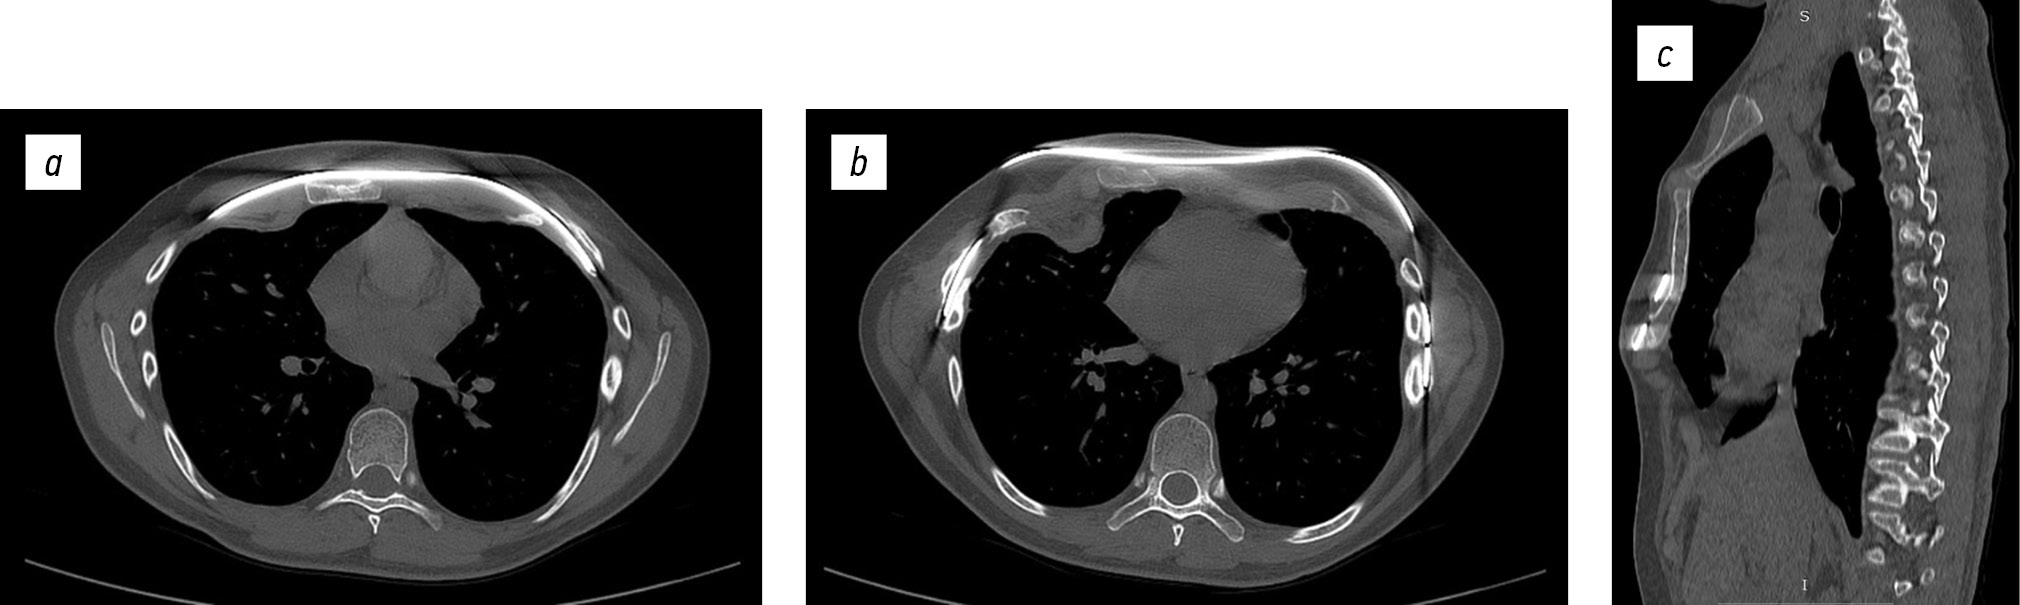

Через сутки от операции в условиях реанимационного отделения и на 5-е сутки выполнена рентгенография грудной клетки — положение металлических пластин правильное, стабильное, легкие расправлены, их пневматизация не нарушена, очаговых и инфильтративных изменений не выявлено (рис. 3).

Рис. 3. Рентгенограмма грудной клетки: на 1-е (а), на 5-е (b) сутки после оперативного лечения.

На 6-е сутки выполнена КТ грудной клетки — положение металлических пластин стабильное. Небольшое скопление воздуха в верхушке легкого без признаков сдавления. Очаговых и инфильтративных изменений не выявлено (рис. 4).

Рис. 4. Компьютерная томограмма грудной клетки после оперативного лечения: горизонтальная плоскость (а, b), сагиттальная плоскость (c). Индекс Галлера 2,19, угол ротации грудины 3° — симметричная, индекс компрессии 0,8.